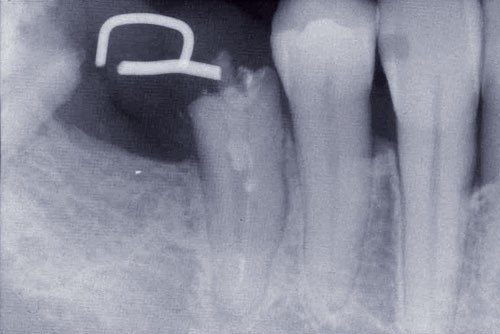

Une patiente âgée de 45 ans consulte à la fin des années 1990 avec une contention en échelle au maxillaire afin de soulager les mobilités des dents antérieures.

Les examens cliniques et radiographiques montrent une parodontite chronique généralisée (fig. 1a à m).

La patiente, en bonne santé, ne fume pas.

Nous décidons d’entreprendre une thérapeutique initiale parodontale classique dans tous les secteurs, y compris l’extraction de 24, un bridge de 45 à 48 avec 46 en pontique, un bridge complet de contention de 17 à 27 sur 11 piliers dentaires et une greffe épithélio-conjonctive sur 31. Cette dernière ne sera jamais réalisée. Le bridge maxillaire permettra de réduire le surplomb antérieur et d’améliorer le sourire de la patiente, ce qui constitue l’une de ses demandes.